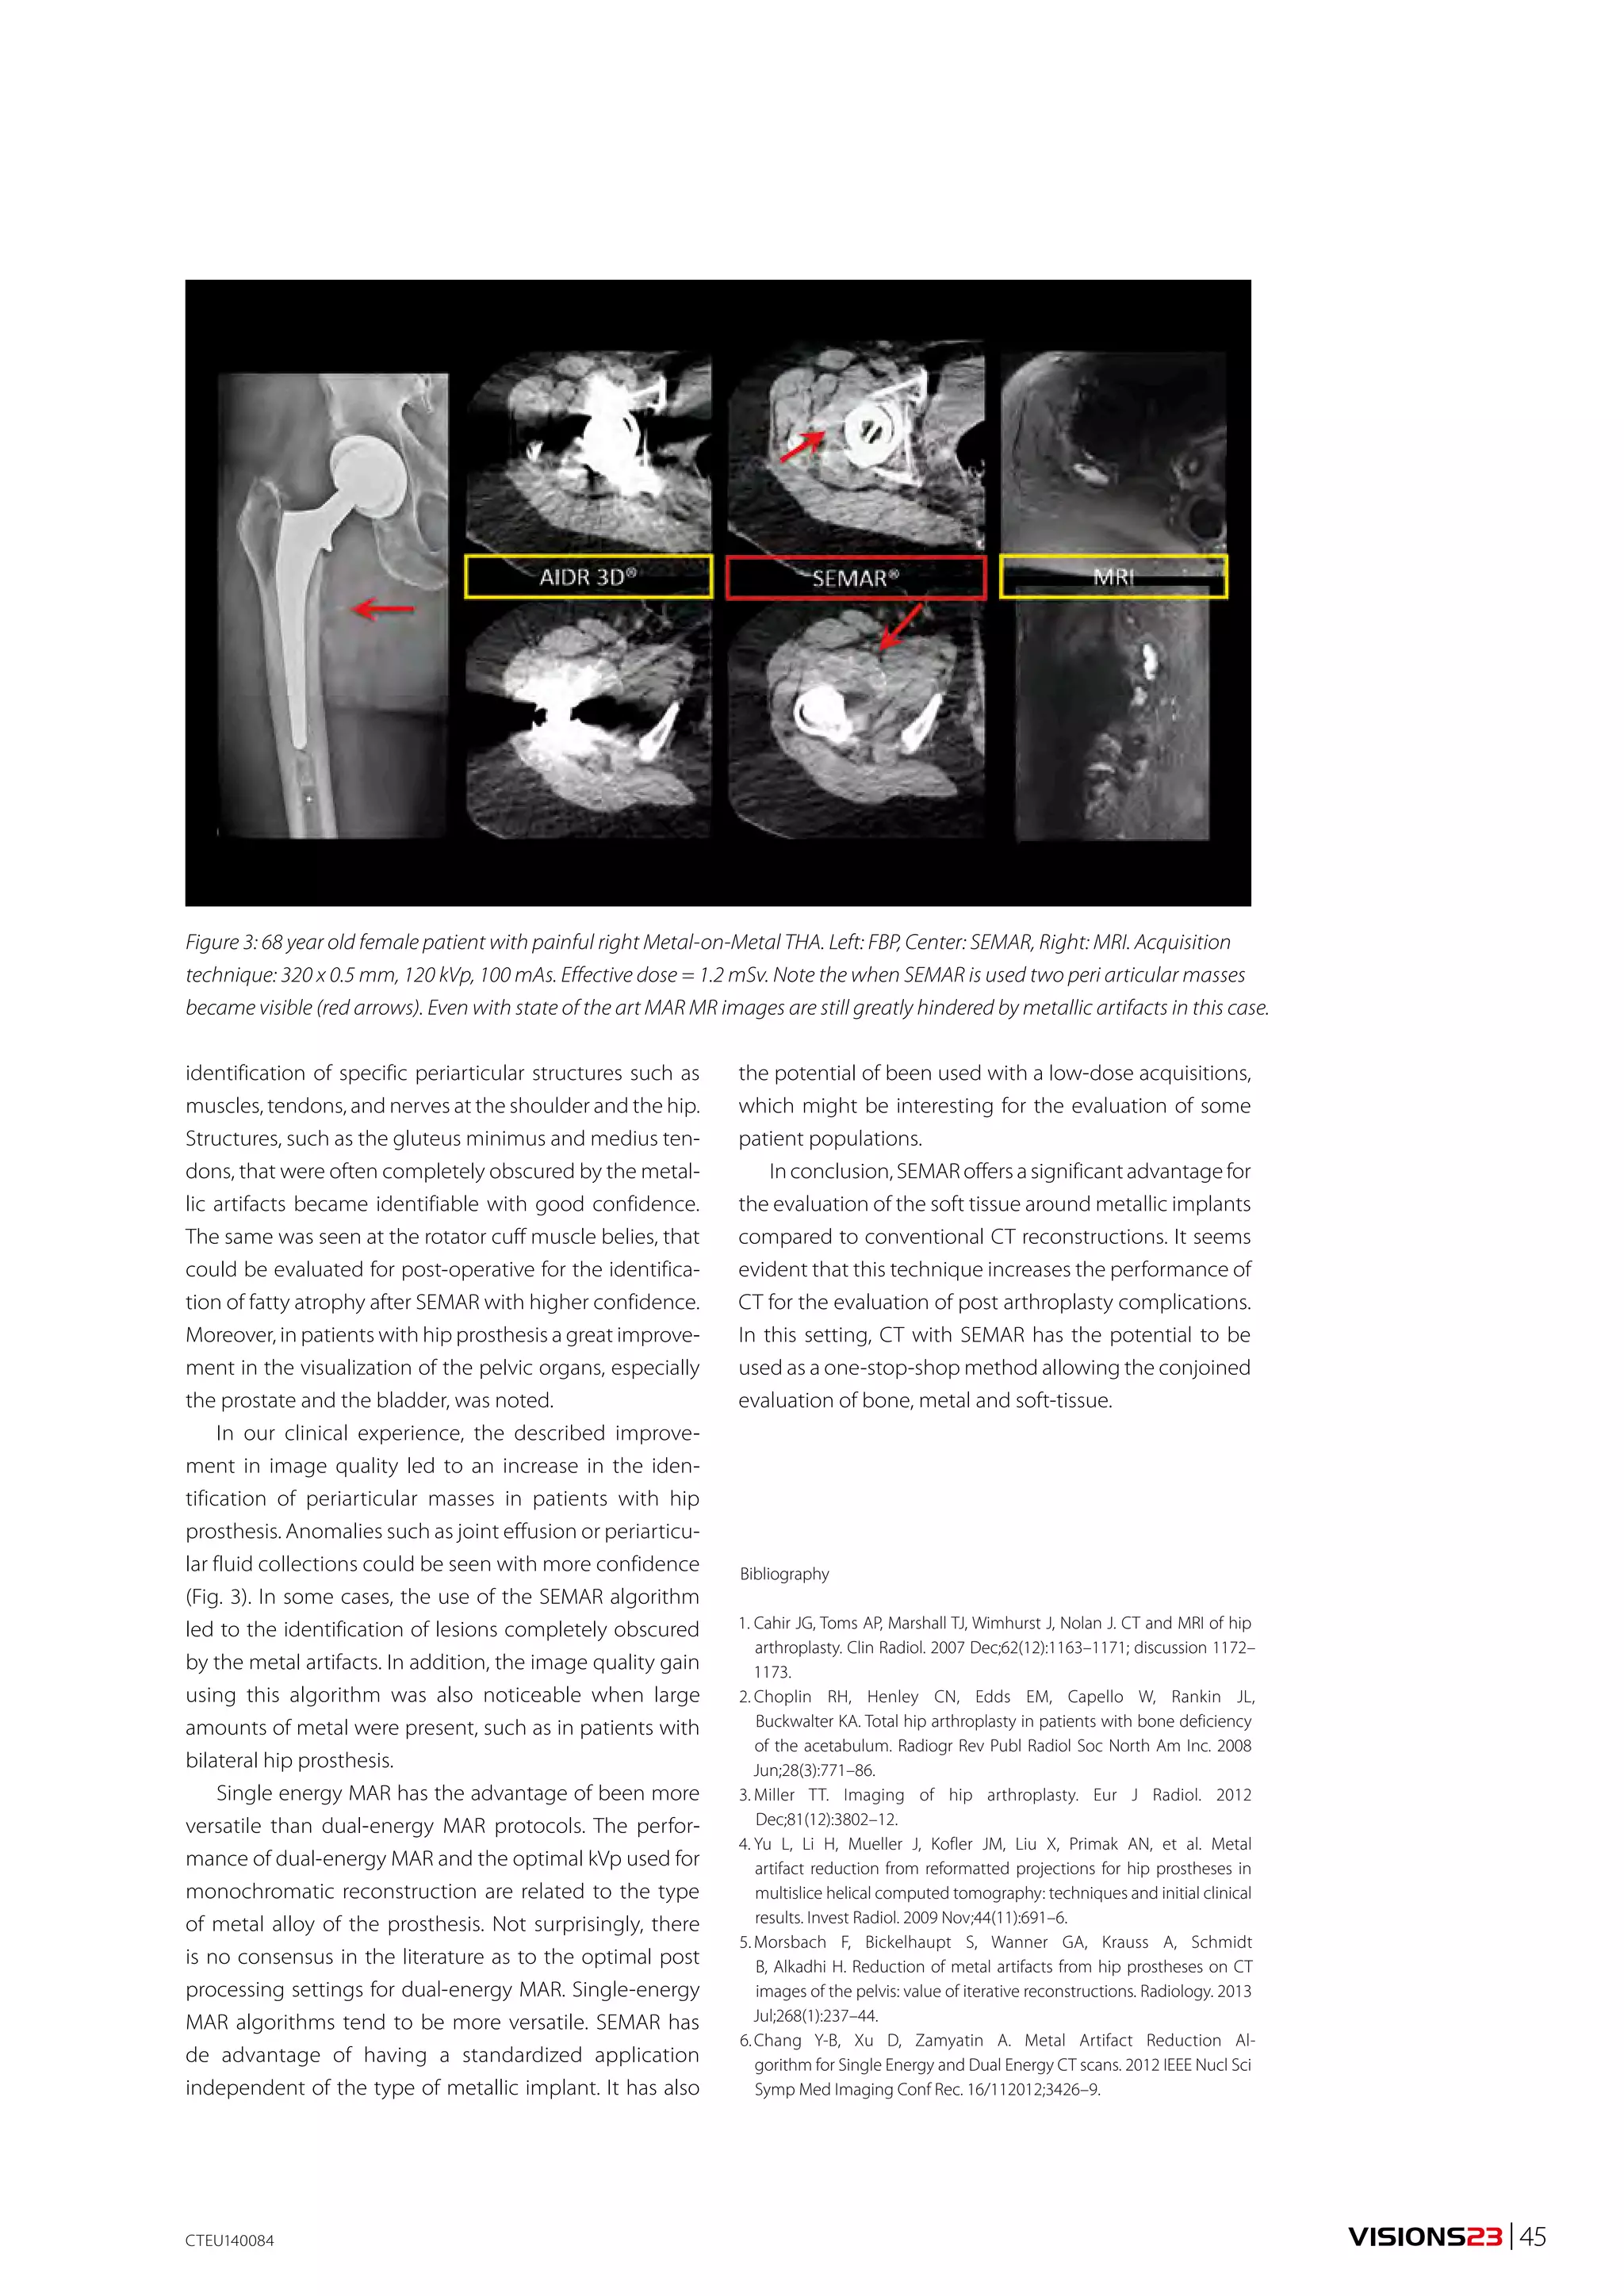

is calculated from the two count values (raw datasets)

obtained by dual energy scanning (Fig. 1). Since the Liner

attenuation coefficient of each material is known, the CT

©2014 32 | VISIONS23 TOSHIBA MEDICAL SYSTEMS

number at a given energy can be determined by combi-nation

with the calculated content, making it possible to

create monochromatic images (keV images).

Novel analysis software which utilizes raw data

based dual energy data available on the Aquilion

ONE includes reduction of beam hardening artifacts,

automatic generation of the best CNR images, virtual

non-contrast image, iodine map, effective atomic num-ber

and electron density imaging. Among these new

technologies, electron density images has gained atten-tion

of radiologists and radiation oncologists because

it is a promising method for generating more accurate

electron density images than conventional methods in

radiotherapy planning.

We performed phantom experiments to verify the

accuracy of this method.

PHANTOM EXPERIMENTS